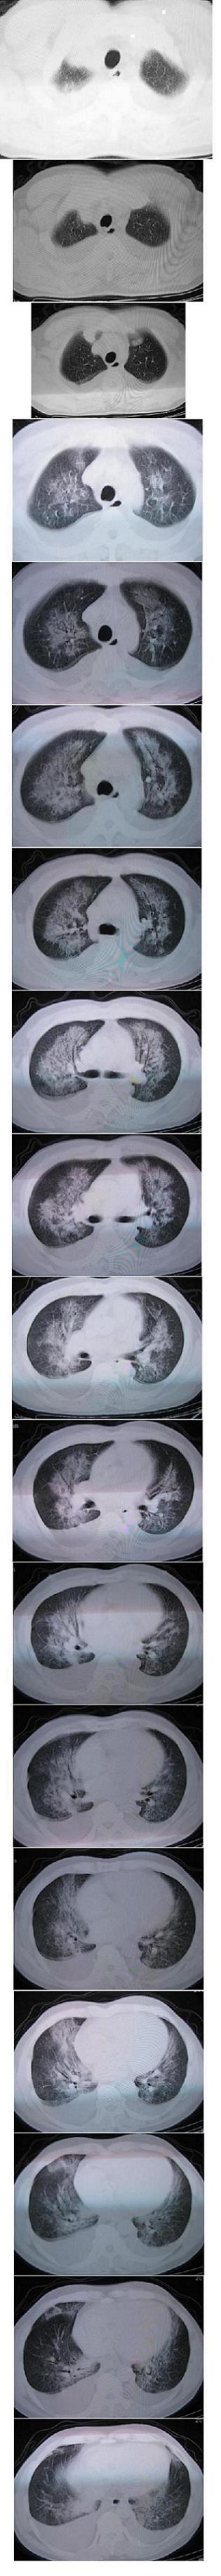

男,36岁,胸闷气喘三天来诊

考虑---肺水肿,双侧胸水。

双肺弥漫性病变 支持肺水肿 双侧胸水

典型肺泡性肺水肿伴双侧胸腔积液。

典型肺泡性肺水肿伴双侧胸腔积液,病因呢?

肺泡性肺水肿并双侧胸腔积液。